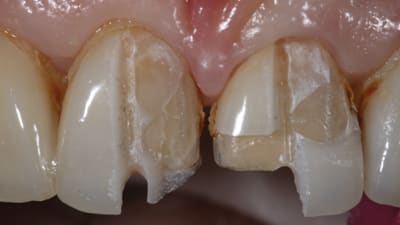

Online Only Endodontics Online Only General Dentistry Correction of a Single Discolored Anterior Tooth Due to Internal Resorption: A Clinical Report By Mario Romero, DDS, Megan Todd, DMD, William Brackett, DDS May 01, 2017 9 min read